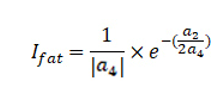

2.2 胖瘦指数定义

通过上述函数图像的特点总结胖瘦指数。

胖瘦指数与四次项系数绝对值成反比,并且与二次项系数和四次项系数的符号关系和绝对值之比有关。胖瘦指数越大,舌体越胖。根据胖瘦特征已知的舌图像样本确定分级标准,可以将舌体描述为“胖”、“不胖不瘦”、“瘦”3种类型。

其中a4为四次项系数,a2为二次项系数。

将得到4次多项式拟合曲线系数代入如下公式,计算胖瘦指数。通过胖瘦指数来判断用户舌体的胖瘦。

其中a4为四次项系数,a2为二次项系数。

胖瘦值数越大说明舌体越宽大,胖瘦指数越小说明舌体越瘦小;胖瘦指数位于4.3-7.8范围内是正常舌,小于4.3是瘦小舌,大于7.8是肥大舌。